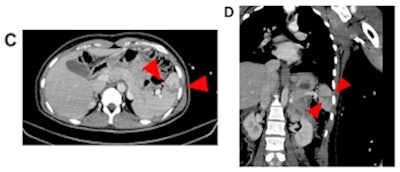

Most conditions related to intimate partner violence are fractures in the face (48.3%), fingers (9.9%), or upper trunk (9.8%), and it can be easy to interpret them as routine trauma, according to the authors. That's why radiologists should thoroughly review the medical history of cases that are suspicious for domestic abuse, discuss these cases with the referring physician, and conduct a private conversation with the patient, educating them on available resources for victims, the authors wrote.